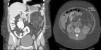

Observación clínicaMujer de 33 años derivada como candidata a TxP por neumotórax derecho persistente a pesar de drenaje endotorácico. Entre sus antecedentes destacaba el ser exfumadora con consumo acumulado poco significativo, neumotórax derecho en el año previo a la consulta y recidiva precoz tras la retirada del drenaje endotorácico. Inicialmente no presentaba insuficiencia respiratoria y en la espirometría se detectó una obstrucción grave con atrapamiento aéreo e hiperinflación. En los estudios radiológicos era evidente el patrón intersticial bilateral con presencia de múltiples quistes de pequeño tamaño y paredes finas que afectaban a la totalidad del parénquima pulmonar, estando preservada su arquitectura. Con la sospecha clínica de LAM, la paciente presentó un neumotórax izquierdo con colapso pulmonar, realizándose pleurodesis mecánica y una biopsia pulmonar abierta que confirmó el diagnóstico. Ante el deterioro de la función pulmonar y la presencia de un nuevo neumotórax derecho con fuga persistente, se derivó a la paciente a nuestra Unidad de Trasplante Pulmonar. Durante su evaluación, una TC abdominal detectó una masa de densidad heterogénea en riñón izquierdo compatible con un angiomiolipoma renal (fig. 1) y lesiones quísticas en hígado. Se la incluyó en lista de espera para TxP en situación de preferencia nacional y, días más tarde, se le realizó un trasplante unipulmonar derecho sin complicaciones inmediatas.